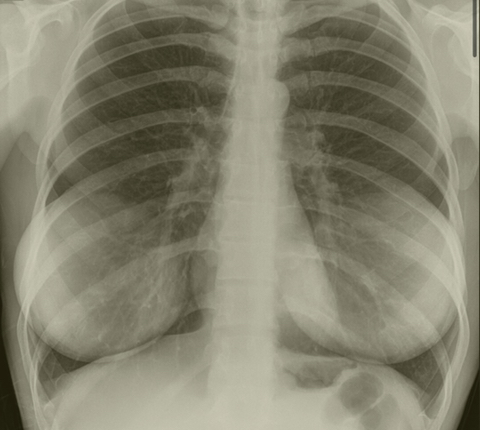

가슴수술 엑스레이